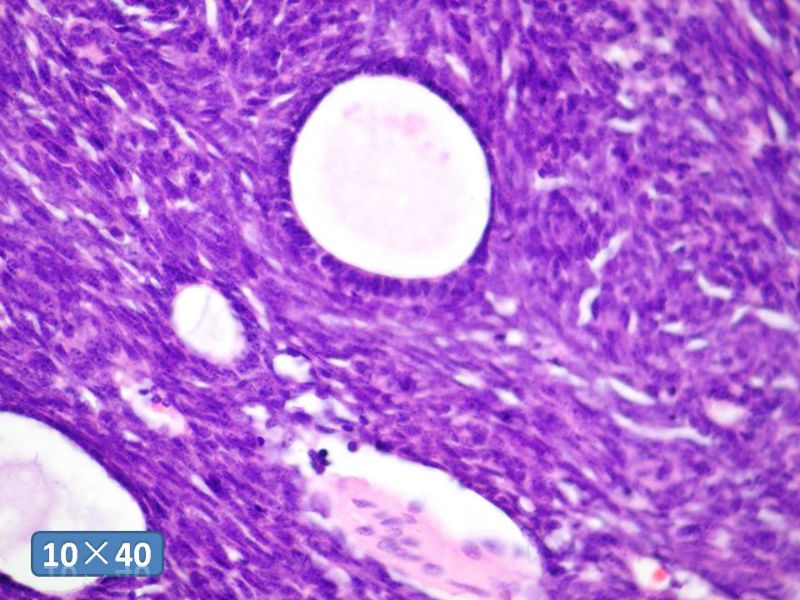

男性,49岁,间断左鼻腔出血3个月。

标签:是嗅母么?

感觉要排除畸胎癌肉瘤。

间质为恶性梭形细胞成分,其间感觉是腺体,两种成分密切相关....

支持嗅神经母细胞瘤(伴有腺体分化)

有上皮和间叶2种结构,畸胎性癌肉瘤是要考虑一下的吧!